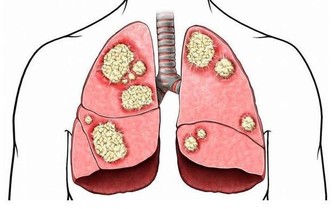

5、口腔白斑

是口腔對外界刺激的最直接反應,假牙不合適、經常抽煙、長期風吹日曬都可能導致這種口腔疾病。

嘴上長泡,暗藏6種致命疾病,做對5件事清火排毒!

多發於唇、舌、牙齦和舌底,早期並無不適感,如果發生糜爛或潰瘍,會有強烈的疼痛感,但如果繼續惡化,斑塊突然快速增大增厚,這時就要特別小心了,可能是癌前病變的信號。